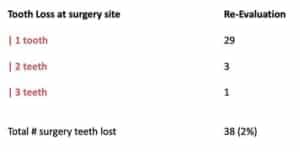

Gebistelementen met furcatie problemen hebben over het algemeen een slechtere prognose. Daarom werd in de praktijk ook het lange termijn resultaat van elementen met furcatiegraad II en III onderzocht. De resultaten laten zien dat na gemiddeld 13-jaar 67% van de elementen behouden konden blijven. Onder de molaren met furcatie II bleef 31,3% stabiel en 32,8% toonde zelf verbetering. Onder de molaren met furcatie III vertoonde slecht 18,9% stabiliteit en maar 8,9% verbeterde. Furcatie III bleek ook geassocieerd met een hoge kans op gebitsverlies. Als kantekening is het belamgrijk om te realiseren dat furcatie niet uitsluitend een parodontale oorzaak kan hebben. Ook endodontische oorzaken, zoals aanwezige laterale kanalen kunnen zorgen voor botafbraak in het furcatiegebied. Dit werd niet apart geëvalueerd.

Gebistelementen met furcatie problemen hebben over het algemeen een slechtere prognose. Daarom werd in de praktijk ook het lange termijn resultaat van elementen met furcatiegraad II en III onderzocht. De resultaten laten zien dat na gemiddeld 13-jaar 67% van de elementen behouden konden blijven. Onder de molaren met furcatie II bleef 31,3% stabiel en 32,8% toonde zelf verbetering. Onder de molaren met furcatie III vertoonde slecht 18,9% stabiliteit en maar 8,9% verbeterde. Furcatie III bleek ook geassocieerd met een hoge kans op gebitsverlies. Als kantekening is het belamgrijk om te realiseren dat furcatie niet uitsluitend een parodontale oorzaak kan hebben. Ook endodontische oorzaken, zoals aanwezige laterale kanalen kunnen zorgen voor botafbraak in het furcatiegebied. Dit werd niet apart geëvalueerd.